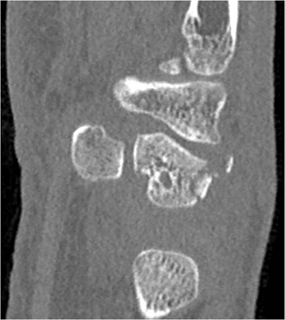

The fracture in this case involves the

Triquetrum

Hamate

Lunate

Navicular